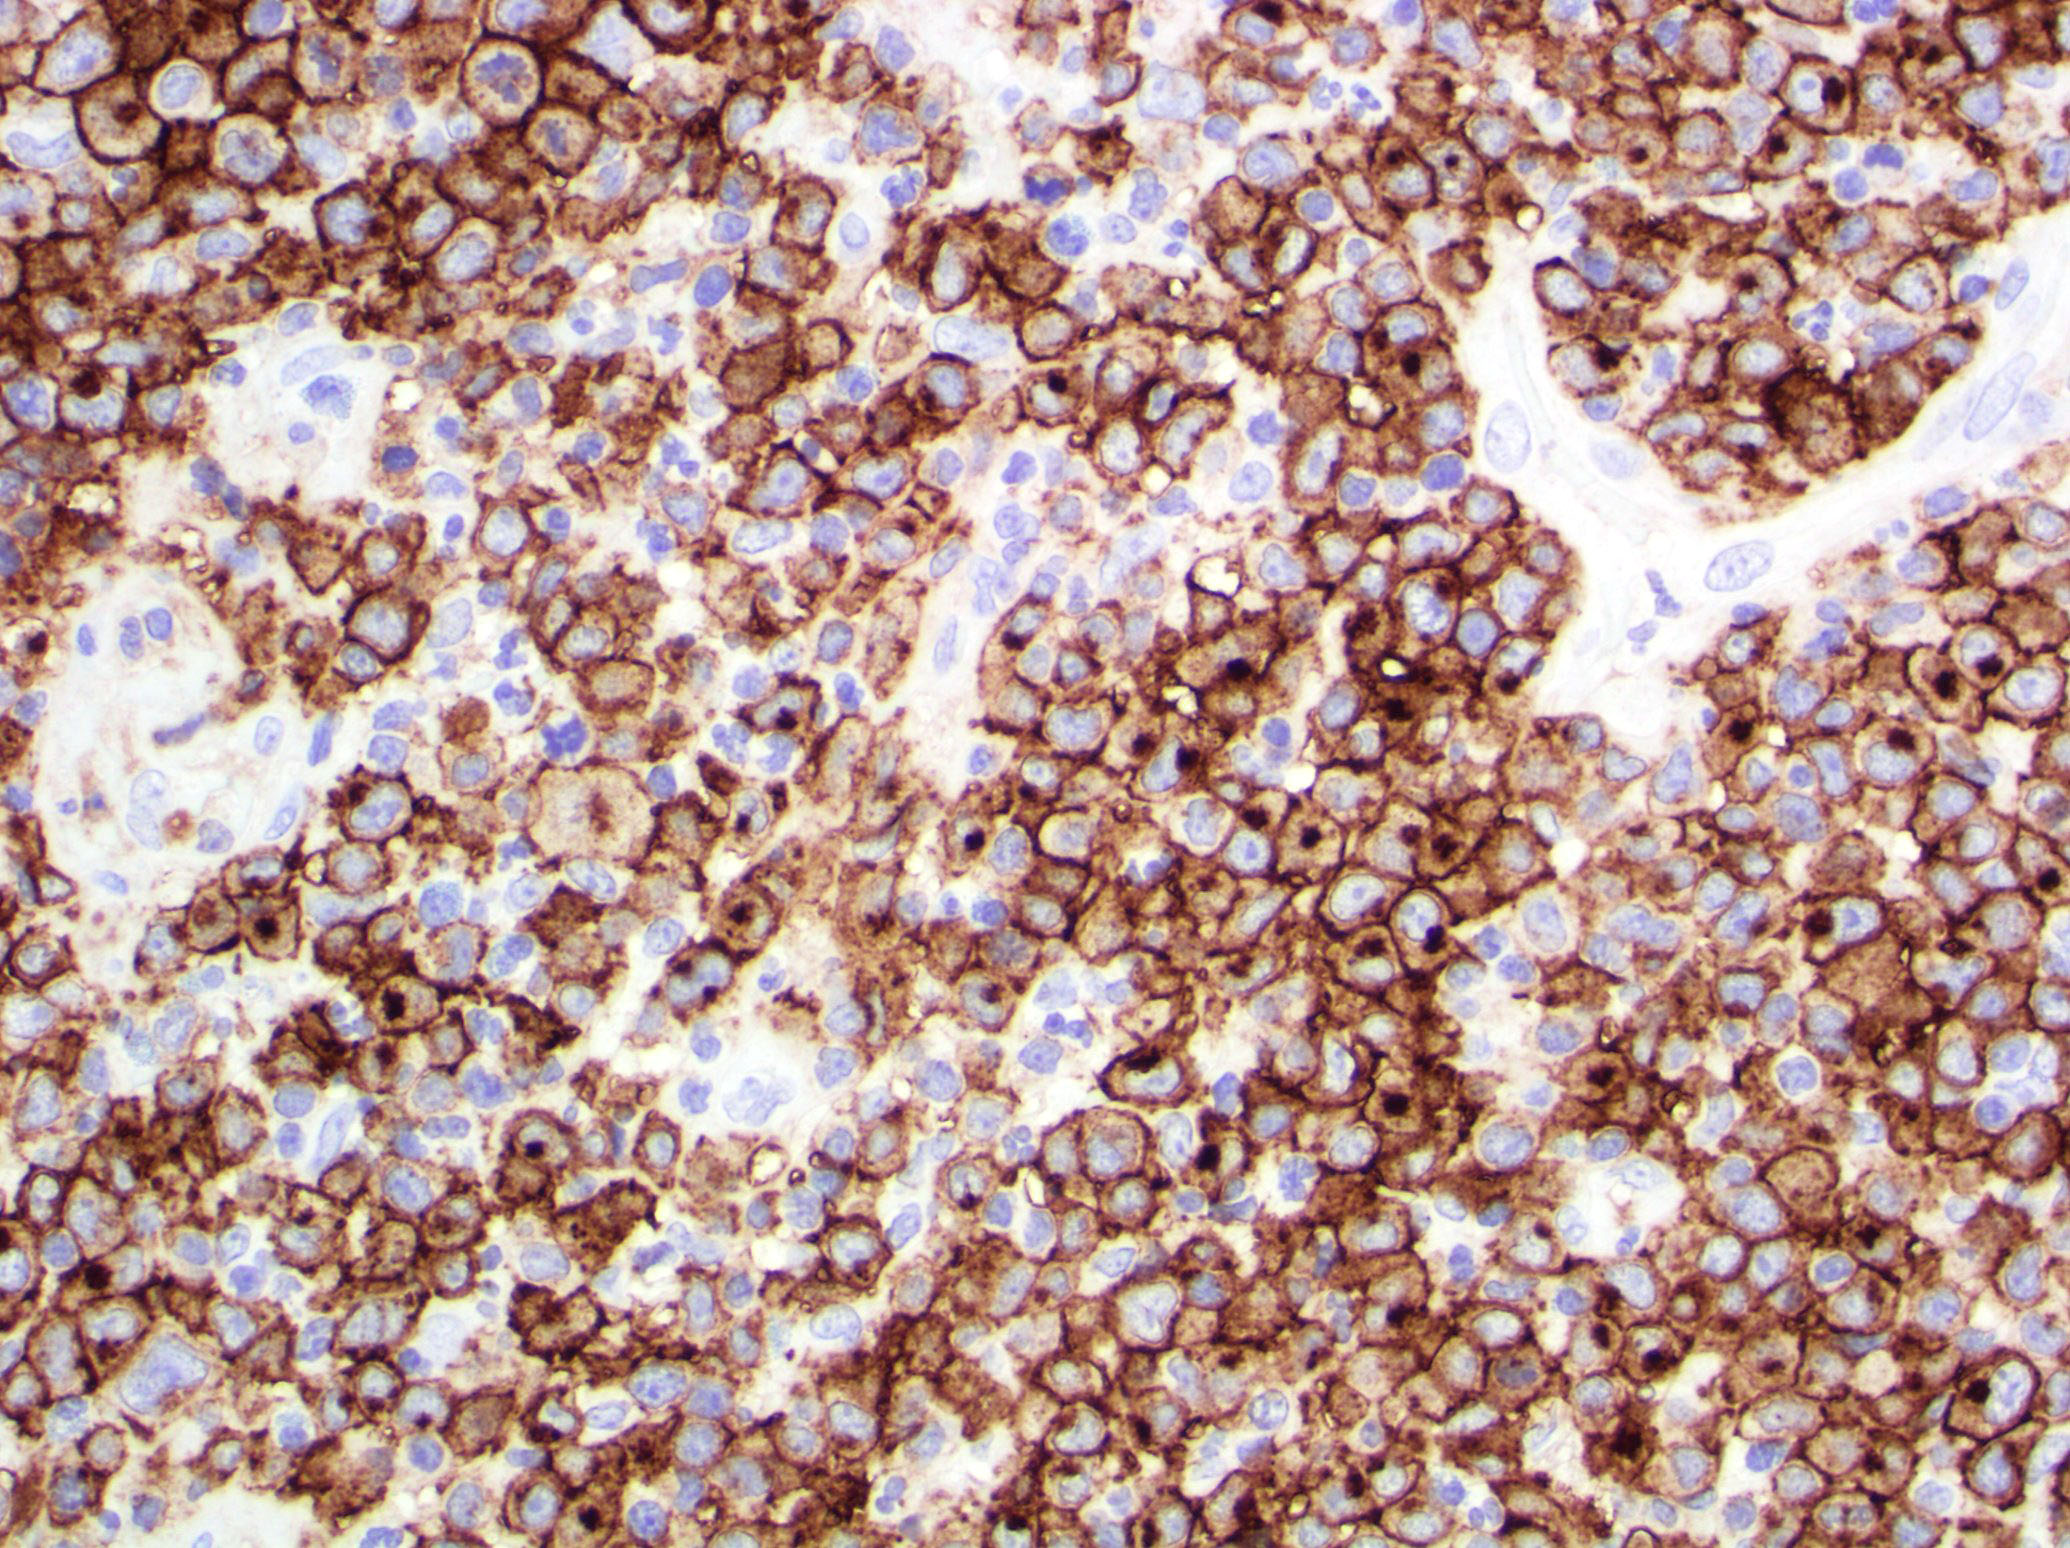

- Type C: sheets of large cells, uniformly positive for CD30, with or without epidermotropism and few admixed inflammatory cells; the lesion mimics primary cutaneous anaplastic large cell lymphoma

Microscopic (histologic) images

Contributed by Roberto N. Miranda, M.D.